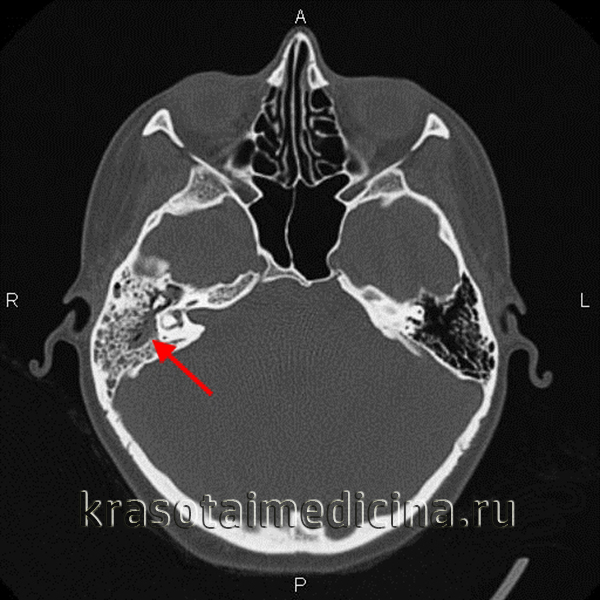

• КТ с КУ:

о Поднадкостничный абсцесс: скопление жидкости возле ушной раковины:

- Утолщение и контрастное усиление наружной стенки отражает воспаление надкостницы

о Абсцесс Бецольда: отграниченное скопление гноя в грудино-ключично-сосцевидной мышце или рядом с ней

о Абсцесс средней черепной ямки:

- Эпидуральное (или в височной доле) скопление жидкости (с контрастированием в виде «кольца»)

о Абсцесс задней черепной ямки:

- Жидкость (эпидурально/в мозжечке) с контрастированием в виде «кольца»

о Возможен тромбоз сигмовидного синуса и/или внутренней яремной вены (ВЯВ)